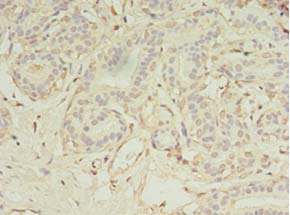

ApplicationELISA, IHC, IF; Recommended dilution: IHC:1:20-1:200, IF:1:50-1:200